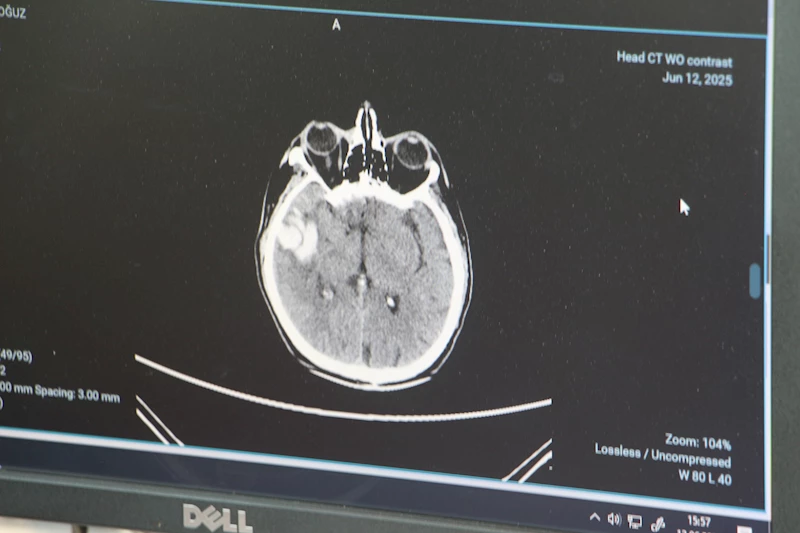

Genellikle 50 yaştan sonra görülen beyin kanaması, son yıllarda gençlerde daha sık görülmeye başlandı. Sebeplerine dikkati çeken Adana Şehir Hastanesi Beyin ve Sinir Cerrahisi Bölümü’nden Doç. Dr. Ali İhsan Ökten, bunların daha çok ‘arteriyovenöz malformasyon’ ve ‘anevrizma’ kaynaklı yaşandığını söyledi. Anevrizma, yani kan damarlarının duvarında oluşan baloncuk şeklindeki patolojik genişlemeler kaynaklı yaşanan beyin kanamalarının 100 binde 10 ile 15 kişi arasında görüldüğünü dile getiren Doç. Dr. Ali İhsan Ökten, “Gençlerde görülme oranı giderek artıyor” dedi.

Stres ve yanlış beslenme alışkanlıklarının bu durumu tetiklediğinin altını çizen Doç. Dr. Ökten, “Gençlerin beslenme alışkanlıklarındaki değişiklikler, genetiği değiştirilmiş gıda tüketimi, çevresel faktörler, iklim değişiklikleri gibi nedenlerle tansiyon oranlarında ciddi olarak bir yükselme var. Tansiyon yüksekliği eskiye oranla gençlerde daha sık görülüyor. Bu da zamanla damarları zayıflatıyor. Buna bağlı olarak da beyin kanamaları daha sık oranda görülüyor” diye konuştu.